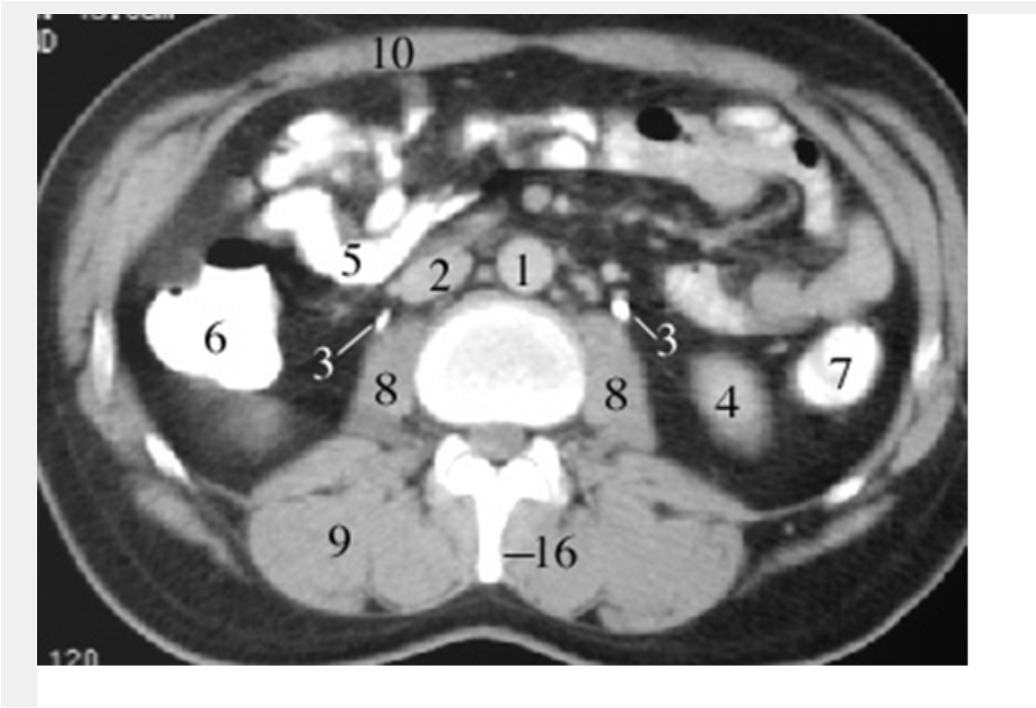

2

aorta

4

left common iliac artery

3

ureters

1

cecum

8

psoas

9

sacram foramen